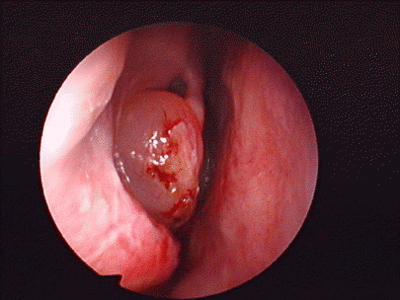

鼻息肉圖片

鼻息肉